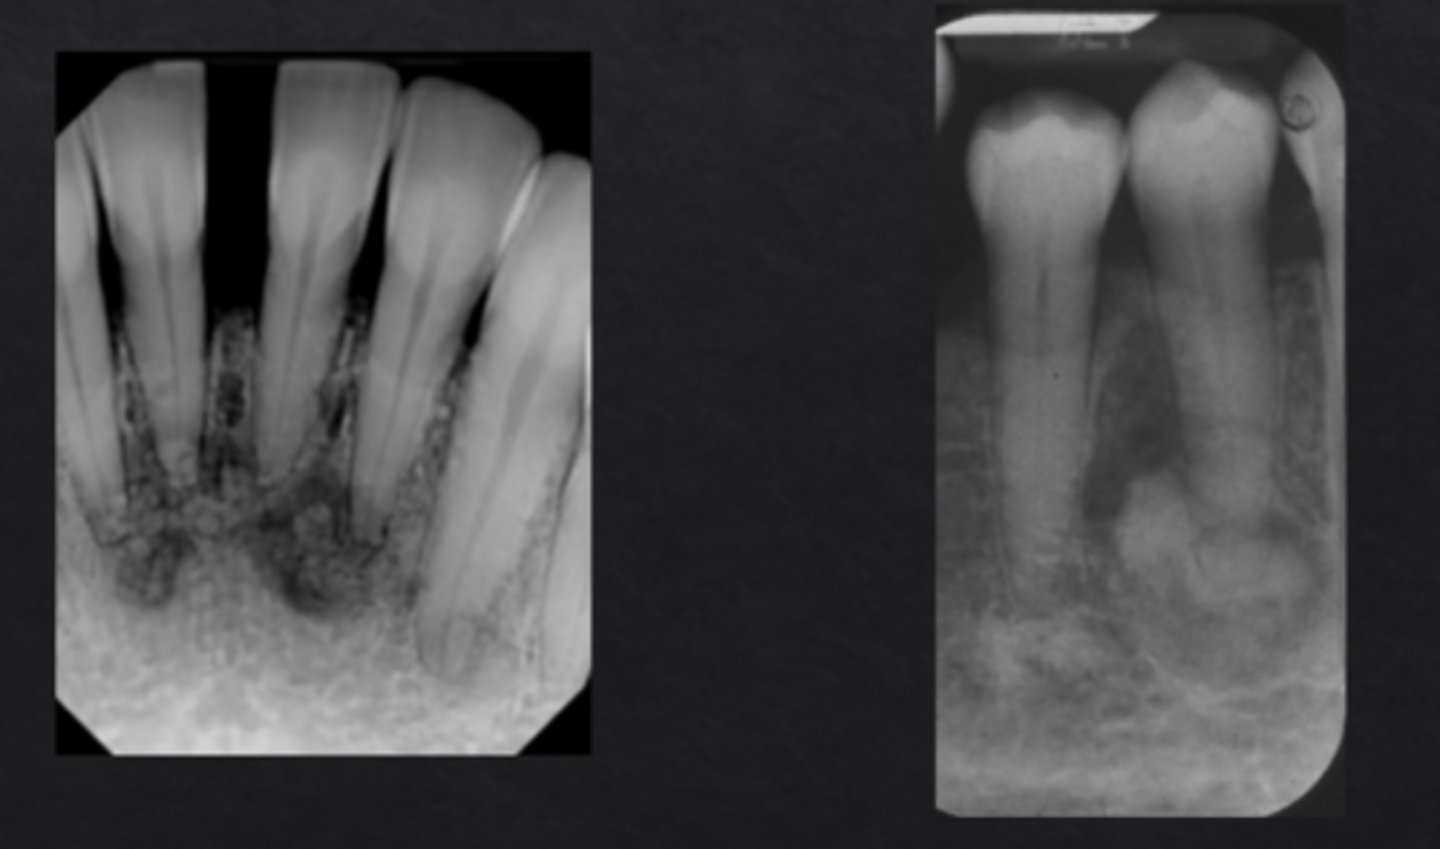

What is cemento-osseous dysplasia?

Localized bone dysplasia that becomes more calcified over time

Cemento-Osseous Dysplasia: _____ if located in one sextant, _____ if located in more than one sextant

Focal, florid

What demographic most often develops cemento-osseous dysplasia?

Middle-aged females, especially African or East Asian ethnicity

How does cemento-osseous dysplasia appear radiographically?

Preapical radiolucency with central calcifications, will become more calcified over time (may lose radiolucent rim)